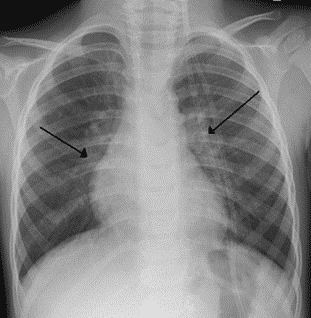

Chest radiograph of an infant showing bilateral pulmonary hyperinflation in RSV

X-ray of a child with RSV showing the typical bilateral perihilar fullness of bronchiolitis